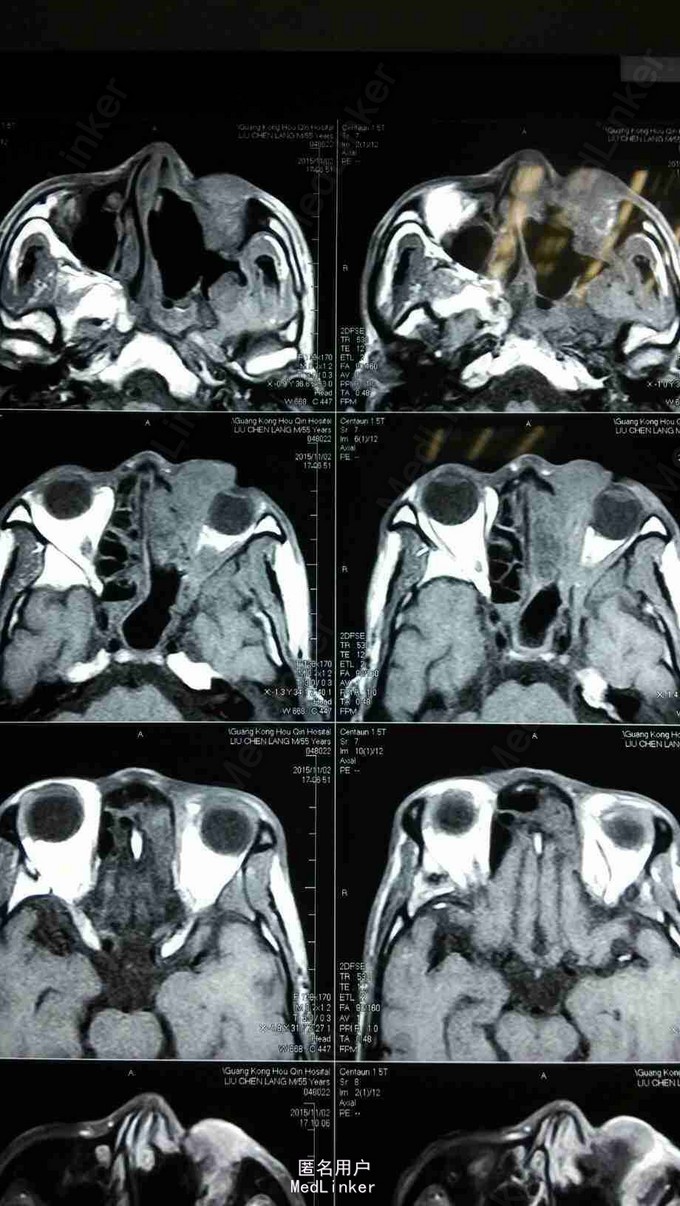

查体:患者神清,消瘦,发音不清,全身浅表淋巴结未见肿大,左眼上睑内侧可见肿物,大小约1*1cm,皮肤红肿,无破溃,质硬,伴压痛,不活动,眼睑闭合不全,睫毛方向正常,眼部可见少量脓性分泌物。 MRI:左侧上颌窦术后改变,左上颌窦顶壁及左眼眶内下方异常信号,考虑肿瘤复发,累及左眶内眦部,前组部分筛窦,内下方肌间隙及上下眼睑内侧份。